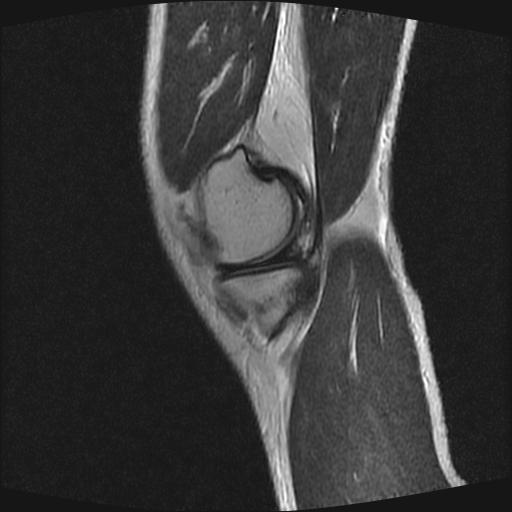

40岁男性,右膝关节外伤,x光平片示,髁间隆突撕脱骨折。

1、前交叉韧带撕裂;

2、外侧半月板后角撕裂;

3、关节腔积液。

前交叉韧带撕裂,关节腔积液.

半月板1-2级损伤   前交叉韧带撕裂伤   关节腔少量积液  诸骨未见新鲜外伤性改变

髁间隆突撕脱骨折;内侧副韧带损伤。

1、内侧副韧带撕裂;

2、前交叉韧带撕裂;

3、滑膜炎伴关节腔积液。

内侧副韧带撕裂及关节腔积液是肯定的,但是前交叉撕裂确定吗?会不会有容积效应的因素,因为前一张前交叉显示清楚,连续性良好,且较光滑。请问楼主有关节镜支持吗?我们医院也经常有这样的患者,但苦于没有关节镜,而无法对照、证实(除非完全断裂),出现了不同的诊断结果只能毫无意义的争论。

1、前交叉韧、内侧副韧带撕裂;

3、关节腔积液。4、髁间脊撕脱骨折。

除了关节积液外并无韧带撕裂,acl胫侧附着点有2束,正常情况下脂肪信号。此病例应加做压脂像以便观察是否有骨损伤。